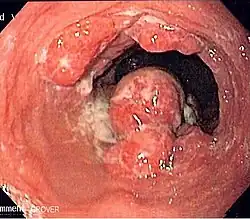

| Endoscopic image of an esophageal adenocarcinoma | |

Although an occlusive tumor may be suspected on a barium swallow or barium meal, the diagnosis is best made with an examination using an endoscope. This involves the passing of a flexible tube with a light and camera down the esophagus and examining the wall, and is called an esophagogastroduodenoscopy. Biopsies taken of suspicious lesions are then examined histologically for signs of malignancy.